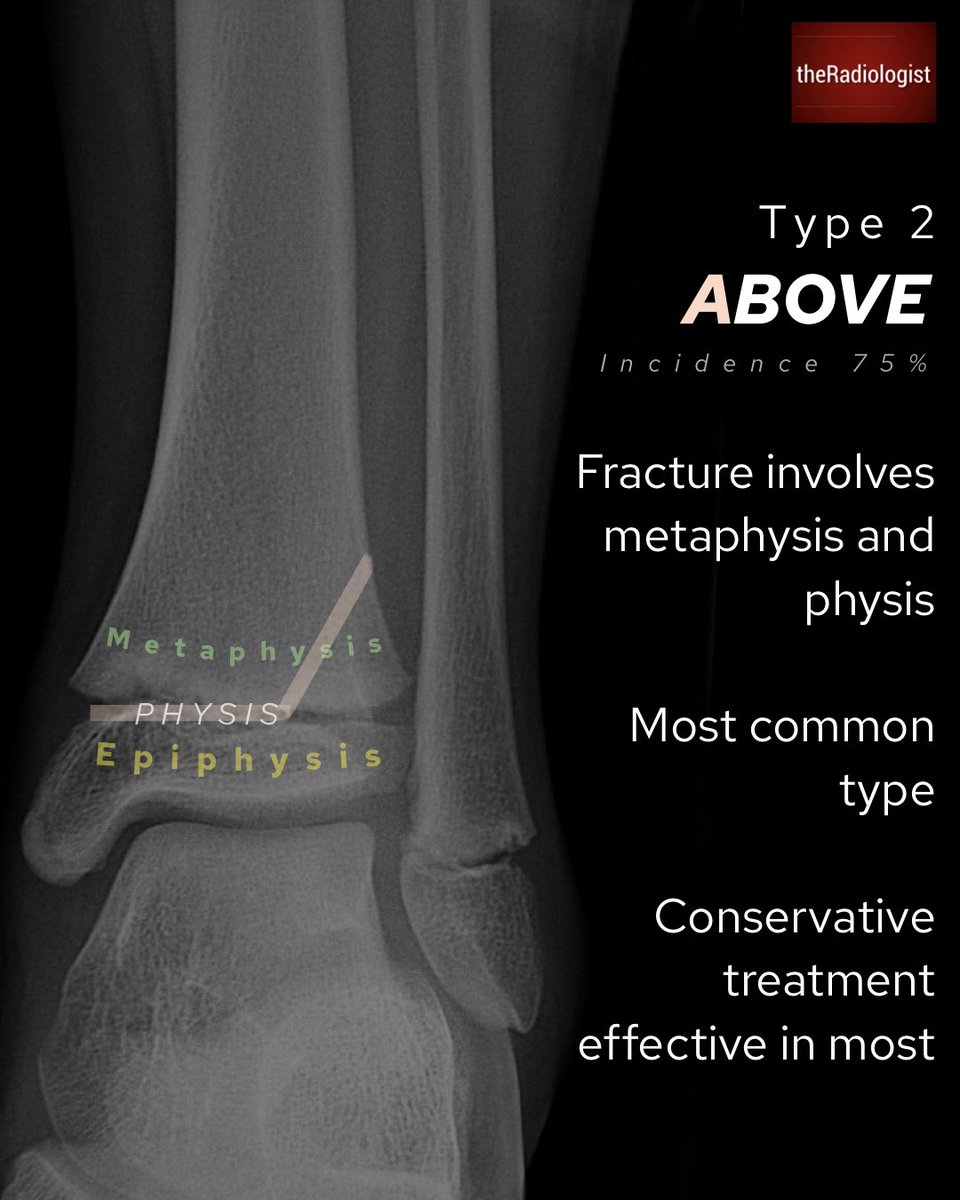

Salter Harris classification for fractures involving the growth plate in children

Mnemonic SALTR